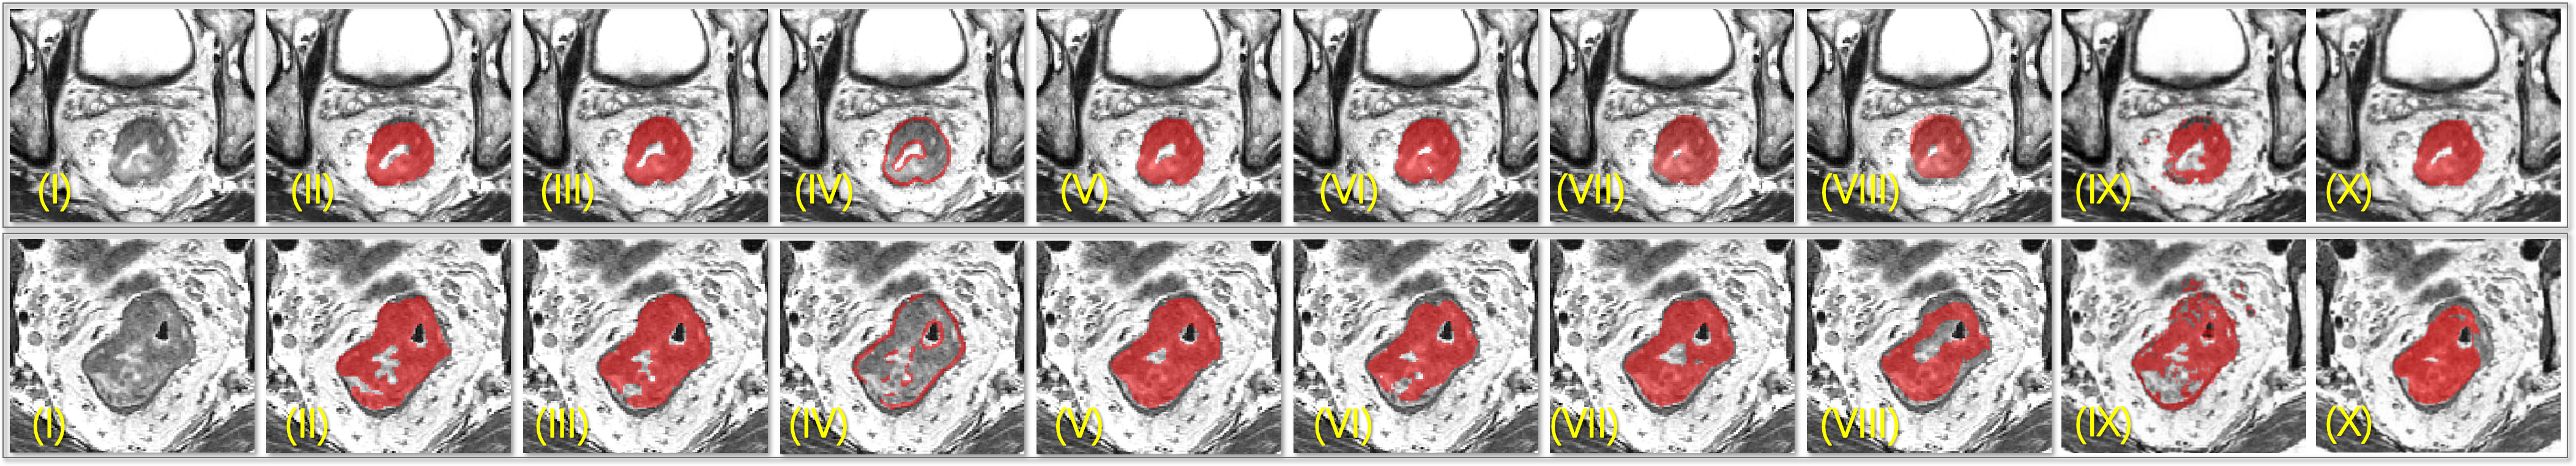

Refer to caption

Figure 5: (I) Cancerous region, (II) Expert delineation, (III) Proposed method(predicted regions), (IV) Proposed method (predicted contours) (V) 3D U-Net+DL[9] (Ensemble) (VI) 3D U-Net[8] (VII) 3D FCN+3D U-Net (VIII) 3D Mask R-CNN[37](IX) Super-Voxel clustering[4](X) 2D kU-Net+LSTM[16]

For evaluation, four-fold cross-validation was conducted on 64 scans and their mean scores are reported in TABLE. 2. Comparison of predicted masks between different methods is illustrated in Fig. 5; Eight volume predictions are illustrated in Fig. 6.